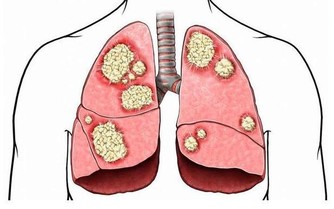

胃癌是發生於胃部上皮組織的惡性腫瘤,常以上腹部不適、疼痛、嘔吐、反胃、嘔血、黑便、消瘦、貧血、上腹部包塊等為其主要臨床表現。

癌前狀態與癌前病變

癌前病變嚴格意義上分兩種,一個叫癌前狀態,一個叫癌前病變,癌前狀態是指患了某些有可能轉化成胃癌的疾病。

癌前病變是指在上述疾病過程中已經發生胃黏膜的不典型增生,這兩類有時統稱為癌前病變。

實際上術語一個是癌前狀態,真正發生了異常增生,從量變到質變才叫癌前病變。

其實所有的腫瘤都是自己身體組織發生了惡變,都是從良性到惡性的過程,所以胃癌也同樣,在它從良性變到惡性的中間過程通常叫癌前病變,這種癌前病變在症狀上、感覺上通常是感覺不到的,需要做檢查,往往要在胃鏡下取病理看看處在一個什麼狀態。

胃的癌前期病變

1.異形增生與間變:前者亦稱不典型增生,是由慢性炎症引起的可逆的病理細胞增生,少數情況下可發生癌變。胃間變則癌變機會多。

2.腸化生:有小腸型與大腸型兩種,小腸型(完全型)具有小腸黏膜的特徵,分化較好。大腸型(不完全型)與大腸黏膜相似,又可分為2個亞型:Ⅱa型,能分泌非硫酸化黏蛋白;Ⅱb型能分泌硫酸化黏蛋白,此型與胃癌發生關係密切。